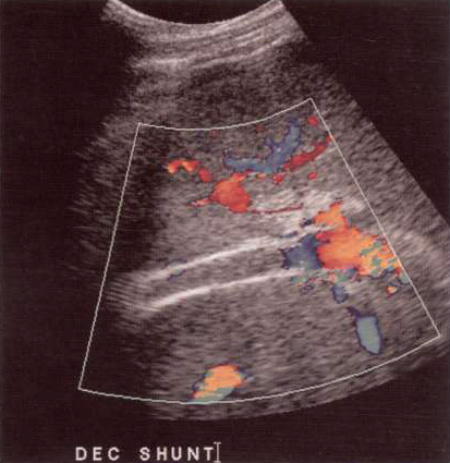

При исследовании портосистемных анастомозов основной задачей УЗИ является оценка проходимости шунтов с помощью методов цветовой, спектральной и, возможно, усиленной допплерографии. УЗИ помогает оценить состояние TIPS, однако спленоренальные, мезокавальные и портоковальные анастомозы, как правило, закрыты газами кишечника (фото 9).

Фото 9. Портокавальный шунт. А – цветовая допплерограмма показывает проходимый портокавальных шунт между дистальным отделом воротной вены и нижней полой вены (IVC). В – спектральная допплерограмма демонстрирует кровоток, направленный по шунту от печени в сторону нижней полой вены